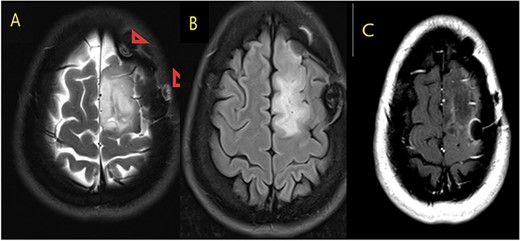

Our patient is a 31-year-old female who presented to the emergency department due to two episodes of generalized tonic colonic seizures. Upon presentation, the patient was administered with supplemental oxygen. She was drowsy and confused while exhibiting signs of right-sided hemiparesis and paralysis. Her pupils were 3 mm and reacted briskly while she showed good left-sided localizing. Her seizures terminated after intravenous administration of midazolam at 5 mg. Further, it was known that she has been symptomatic for 1 month and had been suffering from episodes of seizures, with shaking and tremors of upper limbs, and brief episodes of blackouts for about a minute. These episodes were associated with headache and nausea but were self-limited. Seizures recurred two to three times per week. She denied any fall, tongue bite, loss of consciousness, and limb weakness or numbness. A computerized tomography (CT) scan was suggested, which showed left high parietal hypodensity with vasogenic edema (Fig. 1). She was recommended Keppra 1.5 g and dexamethasone 12 mg. Further, a contrast MRI of the brain was performed (Fig. 2). After a thorough evaluation of the patient’s medical records and current condition, it was decided to proceed with an excision of the tumor using the AC technique. To foster trust and comfort, the same anesthesia and surgical teams were assigned to the patient. Before the procedure, the patient was fully informed about the nature of the procedure and the possibility of a failed outcome or further need for a conversion to general anesthesia. To assess the patient’s cognitive and language abilities, preagreed questions and exercises were performed. These included memory-related queries, such as asking for the patient’s phone number and the names of her dog, and motor commands, such as squeezing a squeaky toy. The patient was prepared for awake navigator-assisted left frontal craniotomy for excision of the left frontal lobe space-occupying lesion, which was suspected to be either a low-grade glioma or fibrous dysplasia. During the surgical procedure, a central line was placed in the right jugular vein using ultrasound, followed by the insertion of a right radial arterial line, a urinary catheter, and two additional venous lines. The patient received a continuous flow of 4–6 l of oxygen per minute. To achieve conscious sedation, the patient received infusions of remifentanil and propofol at varying rates. The patient underwent a 5-hour surgical procedure to remove a tumor. During the procedure, the patient was under sedation and was regularly tested for response to predetermined commands. Her conscious sedation level fluctuated, but she never lost consciousness. The removal of the tumor was successful, and postoperative examination revealed normal motor function and cranial nerve function. The patient was taken to the intensive care unit, and postoperative MRI showed a reduction in the size of the mass lesion in the left frontal lobe/superior frontal gyrus along with mild vasogenic edema surrounding it (Fig. 3).

MRI brain with contrast (A) T2, (B) FLAIR, and (C) T1 postcontrast; in comparison to the fore mentioned study; still noted postoperative changes in the form of craniotomy (regression of size of space occupying cortical mass lesion with mild surrounding vasogenic edema in the left frontal lobe/superior frontal gyrus).